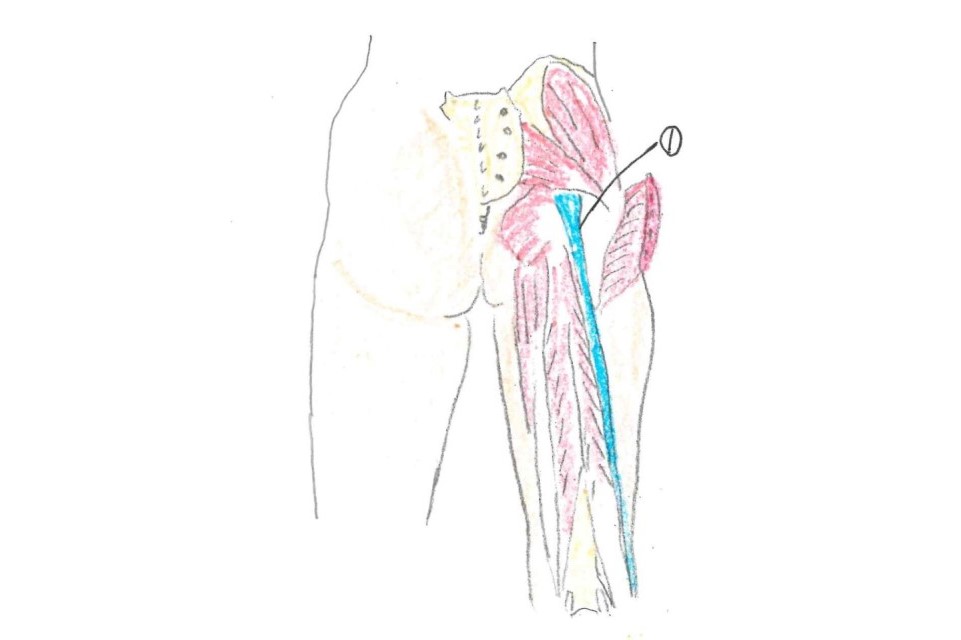

関節痛・神経痛の施術なら

新小岩ひかる接骨院にお任せ

新橋〜松戸・新小岩の整形外科のリハビリ室を長年経験した実績がありますので

関節痛と神経痛には特に自信を持って施術しています。

痛みの原因を探り出し、施術することで完治への近道につながります。

マッサージでごまかすようなことは一切しません。